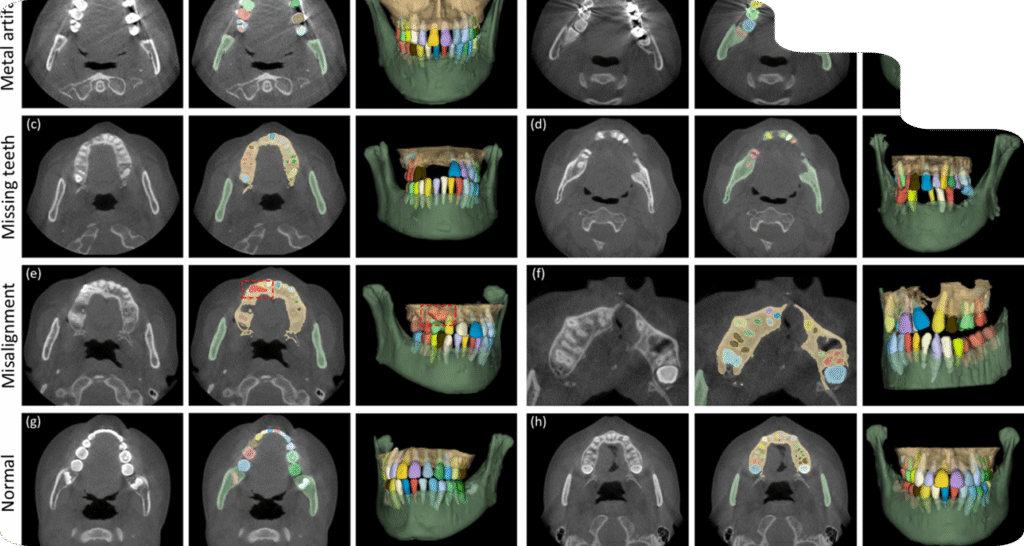

When it comes to your Dental AI model’s success, we at Nidaan offer a specialized service where our team of expert and experienced Oral and Maxillofacial Radiologists collaborates directly with your AI development process. We meticulously verify your dental report data, assist with the high-precision annotation of your datasets (CBCT scans, OPG X-rays, Cephalograms and TMJ x-rays), and aid in the machine learning refinement of your AI systems. This ensures that the data driving your models for all forms of detection, planning and prediction is clinically verified, accurately labeled, and ready for deployment.

Anatomical Segmentation

Precise outlining of teeth, nerves, jaws, sinuses, and airways.

Pathology Labeling

Accurate identification and classification of caries, cysts, tumours, and bone defects.

Ground Truth Creation

Providing the reliable, high-quality data your machine learning models need to perform effectively.